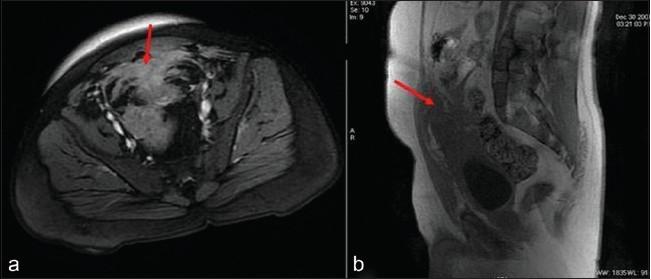

Actinomycosis is a chronic inflammatory condition caused by Actinomyces israeli, a gram positive anaerobic bacterium. It can have a variety of clinical manifestations and can mimic a malignancy. We present one such case of urachal actinomycosis that mimicked a tumor. A 28-year-old man presented with abdominal pain of 20 days duration. Per abdominal palpation revealed a firm mass with ill-defined borders in the suprapubic region. Computed tomography and magnetic resonance imaging scans of the pelvis showed an irregular lesion in the urinary bladder extending to the umbilicus, giving the impression of urachal remnants with inflammation. Peroperatively, an irregular, hard mass measuring 6 × 5 cm, involving the anterior and posterior bladder walls, the appendix, the terminal ileum and sigmoid colon, was seen, which was suspicious for a malignancy. Frozen sections from the mass showed extensive inflammation and a florid fibroblastic proliferation, giving the impression of an inflammatory pseudotumor. The tissue was extensively sampled for paraffin sections and only one of them revealed a colony of Gram, PAS and GMS- positive organisms, conclusive for Actinomycosis. It is important to be aware of this uncommon, yet significant, presentation of a common infectious disease in order to avoid misdiagnosis and over-treatment as a malignancy.

放线菌病是一种由以色列放线菌引起的慢性炎症性疾病,以色列放线菌是一种革兰氏阳性厌氧菌。它可有多种临床表现,且可类似恶性肿瘤。我们报告一例类似肿瘤的脐尿管放线菌病病例。一名28岁男性出现持续20天的腹痛。腹部触诊发现耻骨上区有一个边界不清的实性肿块。骨盆的计算机断层扫描和磁共振成像扫描显示膀胱内有一个不规则病变延伸至脐部,给人以脐尿管残余伴炎症的印象。手术中可见一个大小为6×5 cm的不规则硬块,累及膀胱前壁和后壁、阑尾、回肠末端和乙状结肠,怀疑为恶性肿瘤。肿块的冰冻切片显示广泛炎症和活跃的成纤维细胞增生,给人以炎性假瘤的印象。对组织进行广泛取材制作石蜡切片,其中只有一张切片显示有革兰氏、PAS和GMS阳性菌菌落,确诊为放线菌病。认识到这种常见传染病的这种不常见但重要的表现形式很重要,以便避免误诊和作为恶性肿瘤进行过度治疗。